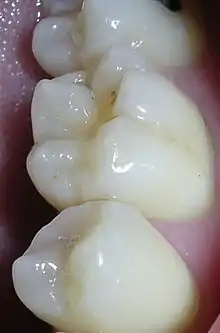

Dental sealants (also termed pit and fissure sealants,[1] or simply fissure sealants)[2] are a dental treatment intended to prevent tooth decay. Teeth have recesses on their biting surfaces; the back teeth have fissures (grooves) and some front teeth have cingulum pits. It is these pits and fissures that are most vulnerable to tooth decay because food and bacteria stick in them and because they are hard-to-clean areas. Dental sealants are materials placed in these pits and fissures to fill them in, creating a smooth surface which is easy to clean. Dental sealants are mainly used in children who are at higher risk of tooth decay, and are usually placed as soon as the adult molar teeth come through.

Dental sealants are a preventive treatment that is part of the minimal intervention dentistry approach to dental care.[4] These sealants are a plastic material placed in the pits and fissures (the recesses on the chewing surfaces) of primary (baby) or permanent (adult) molar and premolar teeth at the back of the mouth. These molar teeth are considered the most susceptible teeth to dental caries due to the anatomy of the chewing surfaces of these teeth, which inhibits protection from saliva and fluoride and instead favours plaque accumulation.[5] This approach facilitates prevention and early intervention, in order to prevent or stop the dental caries process before it reaches the ends stage of the disease, which is also known as the "hole" or cavitation of a tooth.[4] Once the tooth is cavitated, it requires a dental restoration in order to repair the damage, which emphasizes the importance of prevention in preserving teeth for a lifetime of chewing.

Preventing tooth decay from the pits and fissures of the teeth is achieved by dental sealants providing a physical barricade to protect natural tooth surfaces and grooves, inhibiting build-up of bacteria and food trapped within such fissures and grooves. Dental sealants also provide a smooth surface that is easily accessible for both the natural protective factor, saliva and the toothbrush bristles when cleaning the teeth.[6] As dental sealants are clear or white, they are only visible upon close inspection.